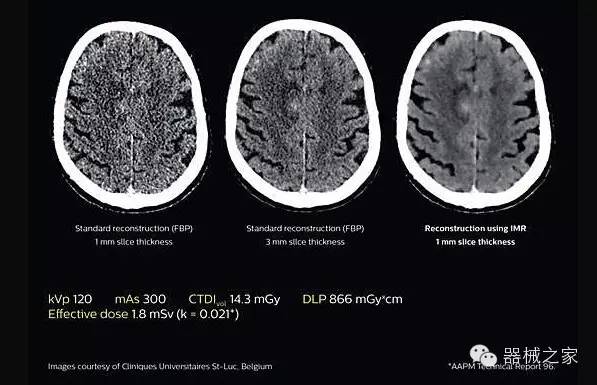

2.腦部顯影